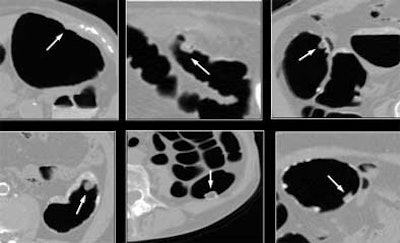

| The presence of untagged or partially tagged stool in images above led to false-positive results with CAD. |

"There were some cases that were partially covered by stool, which were unfortunately missed by CAD," he said. In fact, untagged or partially tagged stool was the principle cause of false-positives (40%), followed closely by haustral folds (39.3%), nonspecific findings (4.1%), stomach or small bowel (4.1%), ileocecal valve (4.1%), extrinsic compression (0.7%), rectal tube (0.1%), and other findings (6.2%) the CAD scheme took as polyps, and which the radiologist would presumably eliminate upon inspection of the CAD results, according to Yoshida.